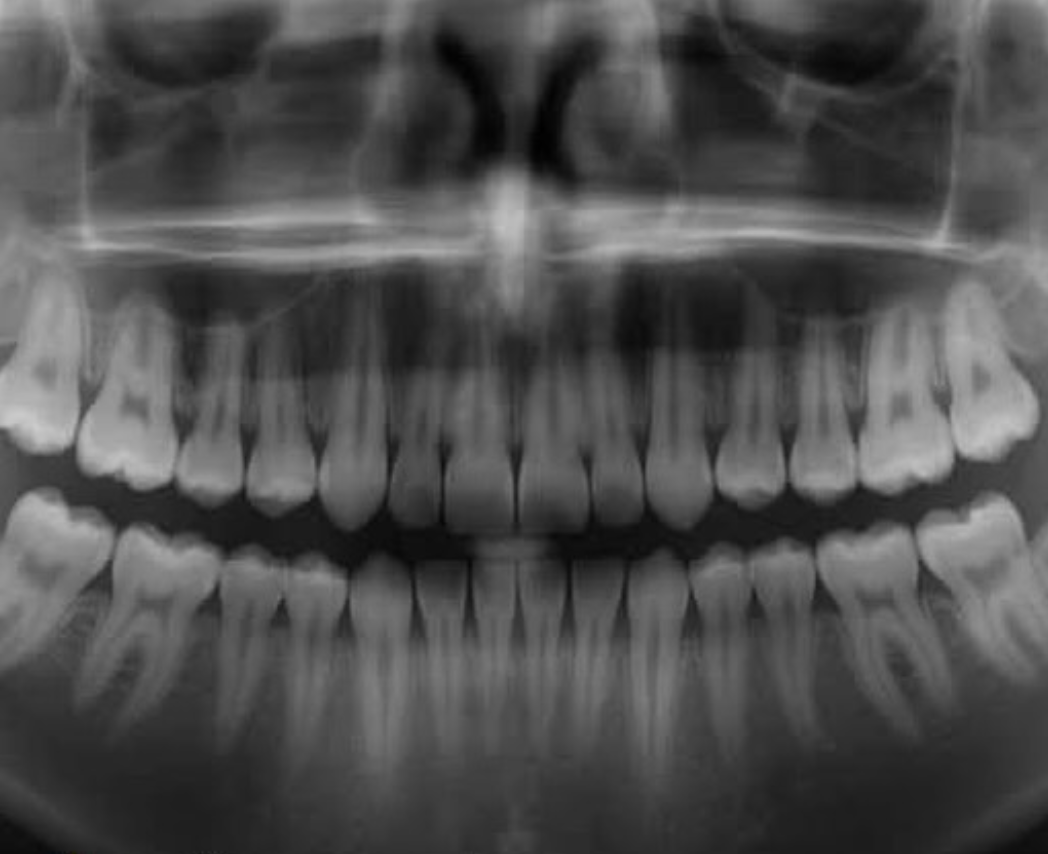

Um grupo de pesquisadores do Instituto de Pesquisa Médica do Hospital Kitano, no Japão, deu um passo gigantesco rumo à regeneração dentária humana. A equipe, liderada pelo Dr. Katsu Takahashi, criou um fármaco capaz de estimular o crescimento natural de novos dentes — uma revolução que pode transformar completamente a odontologia moderna.

O medicamento atua bloqueando a proteína USAG-1, conhecida por inibir a formação dentária. Em testes com roedores, a inibição dessa proteína levou ao surgimento de dentes totalmente formados, um resultado considerado inédito na área da medicina regenerativa.

A descoberta se apoia em décadas de pesquisa e na constatação de que os seres humanos possuem gérmens dentários adormecidos — uma espécie de “reserva” biológica que, se reativada, poderia gerar uma terceira dentição natural. Esse fenômeno já é comum em animais como tubarões e elefantes, que trocam seus dentes diversas vezes ao longo da vida.